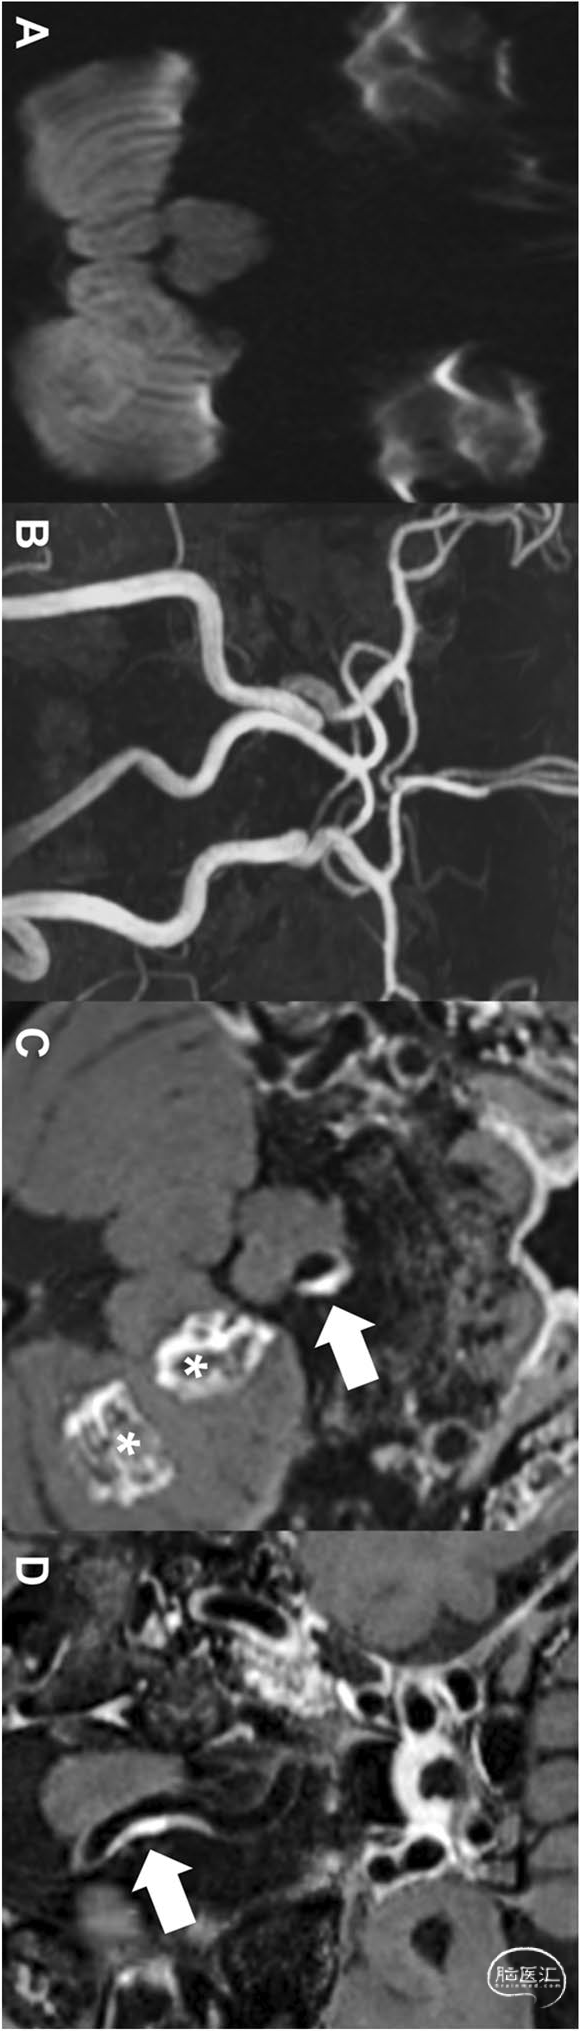

患Bechet综合征的45岁男性,主诉为恶心和呕吐。血管危险因素,包括高脂血症和高血压。24小时动态心电图、超声心动图检查或增强经颅超声心动图未发现阳性结果。DWI(A)显示左侧小脑缺血性病变。MRA几乎无法发现左椎动脉V4段狭窄(B)。增强HRVWI(C,D)上可见左椎动脉斑块明显强化(白色箭头),这是小脑后下动脉血管区域亚急性梗死(C,星号)的原因。根据常规检测,该患者的卒中病因为病因不明,加入HRVWI后,其病因变为大动脉动脉粥样硬化: